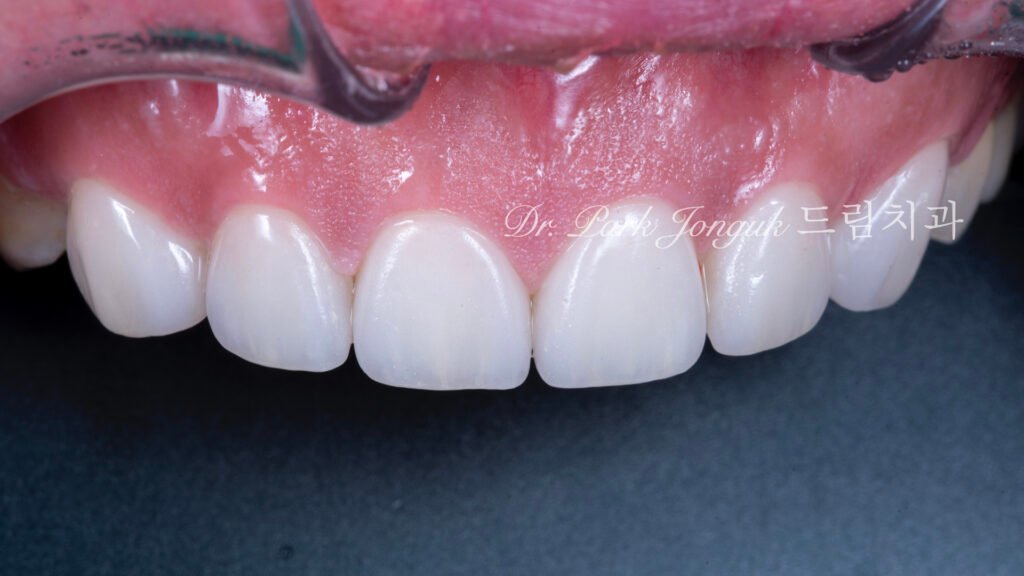

5. 최종 복원: 자연미의 극대화 (사진 6, 7, 8)

5.1 무삭제 라미네이트의 완성

[사진 6, 7, 8 참조] 0%의 삭제율로 완성된 최종 결과물입니다.

- 기능적 보호: 위산에 의해 약해진 치아 표면을 강도 높은 세라믹이 보호막처럼 감싸주어 추가적인 부식을 차단합니다.

- 광학적 재현: 기계로 깎아낸 Monolithic 방식이 아닌, 숙련된 기공사의 **핸드메이드 빌드업(Build-up)**을 통해 자연치 특유의 투명도와 질감을 재현했습니다.

- 심미적 조화: 교정으로 바르게 정렬된 치열 위에 정밀 설계된 라미네이트가 더해져, 부자연스러운 돌출감 없이 조화로운 미소를 완성했습니다.